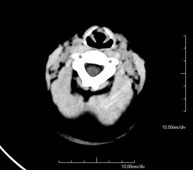

- Neuroradiology

- Skull CT

Radiological test that provides high definition anatomical images of the skull (brain stem, cerebellum, cerebrum, cranial calotte, etc.) using CT (Computed Tomography) equipment. Indicated for: trauma, headache, memory disorders, sudden loss of strength in a limb or half of the body.